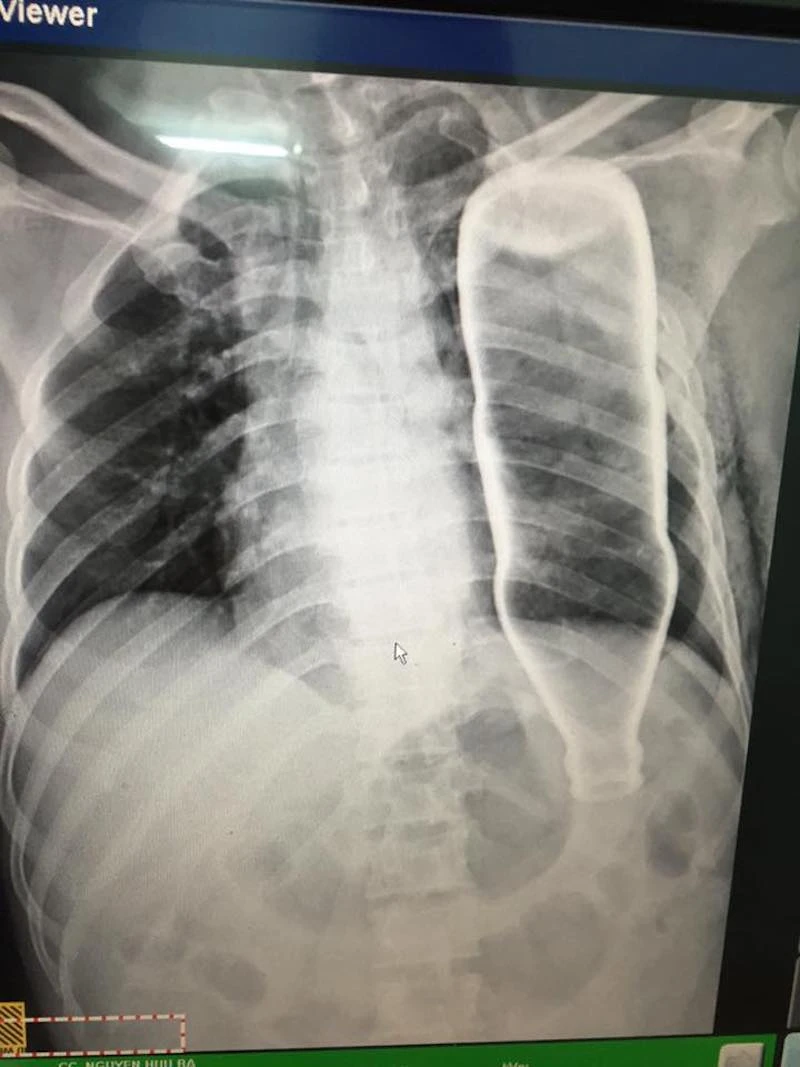

Hình ảnh chai nước qua màn hình chụp X-quang và CT. Ảnh: AB

Sau khi tiếp nhận bệnh nhân, BV đã tiến hành chụp X-quang và CT, các bác sĩ ngỡ ngàng khi thấy một vỏ chai thủy tinh còn nguyên vẹn trong lồng ngực bệnh nhân B.